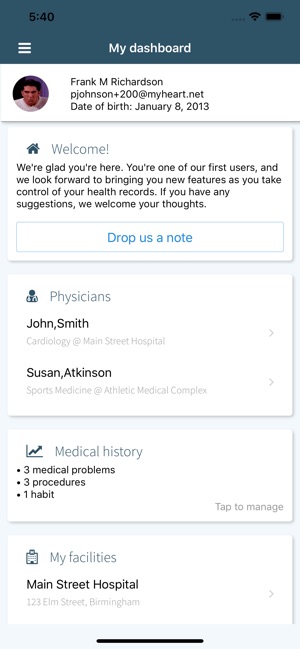

Keeping track of your medical history should not be hard or require you to tote a large binder to all your doctor’s appointments. With VitalEngine Patient, you can carry your entire medical chart in your pockets. Create your free account and you will be able to:

- Manage all your medical problems, procedures, social history and more.

- Keep track of all your medical providers.

Our app is part of the rapidly-expanding VitalEngine network, used by medical providers worldwide. If your doctor’s office is in the VitalEngine network, it will also be able to upload documents and images to your account, so it can provide you with real-time, secure and accessible-anywhere medical information, all in a HIPAA-compliant platform.